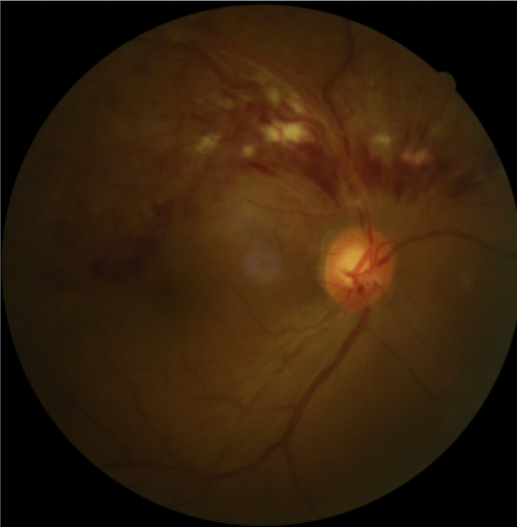

患者劉某,58歲,因右眼視力下降伴(bàn)變形1月入院。既往有高血壓病,血糖偏高病史,左眼視物(wù)不(bú)見10餘(yú)年,經過眼科主治醫(yī)師方(fāng)霏的(de)詳細檢查及(jí)眼底造(zào)影(yǐng)檢(jiǎn)查,發現是患(huàn)上了右眼視網膜分支靜脈阻塞,右眼黃斑水腫,左眼萎縮性黃斑病變(biàn)。劉大叔入院時右眼視力僅0.1 ,需要使用一種新型的生物製劑(jì)(抗 VEGF)治(zhì)療,方霏主治醫師向患者及(jí)家屬交代病情、手術(shù)必要性及相關風險 ,在排(pái)除(chú)了手術禁忌症後,患者及家屬表示同(tóng)意手術治療。次日,方霏主治醫師在患者(zhě)表麵麻醉下進行右(yòu)眼(yǎn)玻璃體藥物注射術,術後患者(zhě)無明顯特殊不適。4周後複查,右眼黃斑水腫明顯減輕,視力由0.1提高至0.6。玻璃體腔注藥術明顯改善了患者視力,患者劉大叔表示十分滿意。

術前眼底照相及眼(yǎn)底(dǐ)造影FFA

術前OCT檢查提示右眼黃斑水腫